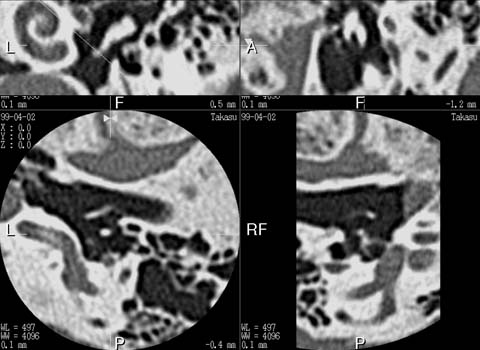

It has been a dream for radiologists to realize the "isotropic voxel" in CT where resolution is the same in x-, y- and z-axis since it will totally eliminate the partial volume averaging effect due to slice thickness. Half millimeter slices provides a true isotropic voxel in 24-cm field of view (FOV) and provides near-isotropic voxels in an 18-cm FOV (see Isotropic voxel). This means that the resolution of coronal and sagittal section is the same as that of an axial slice as shown in our clinical examples. Similar improvement can be observed in body-CT diagnosis with the use of 1-mm slices. I personally believe that this represents evolutional progress not only for CT diagnosis but also for all the slice-based diagnostic modalities.

One of the serious shortcomings in thinner slice scanning is a limited scanning range - the thinner the slice is, the gerater is the scanning time required to cover the target organ(s). Two rows of 0.5-mm detector array will only works for the scanning of small organ such as middle ear. On the contrary, orbita, circle of Willis, facial bone, entire skull and brain or even the cervical and lumber spine are accessible to a 4-row system.